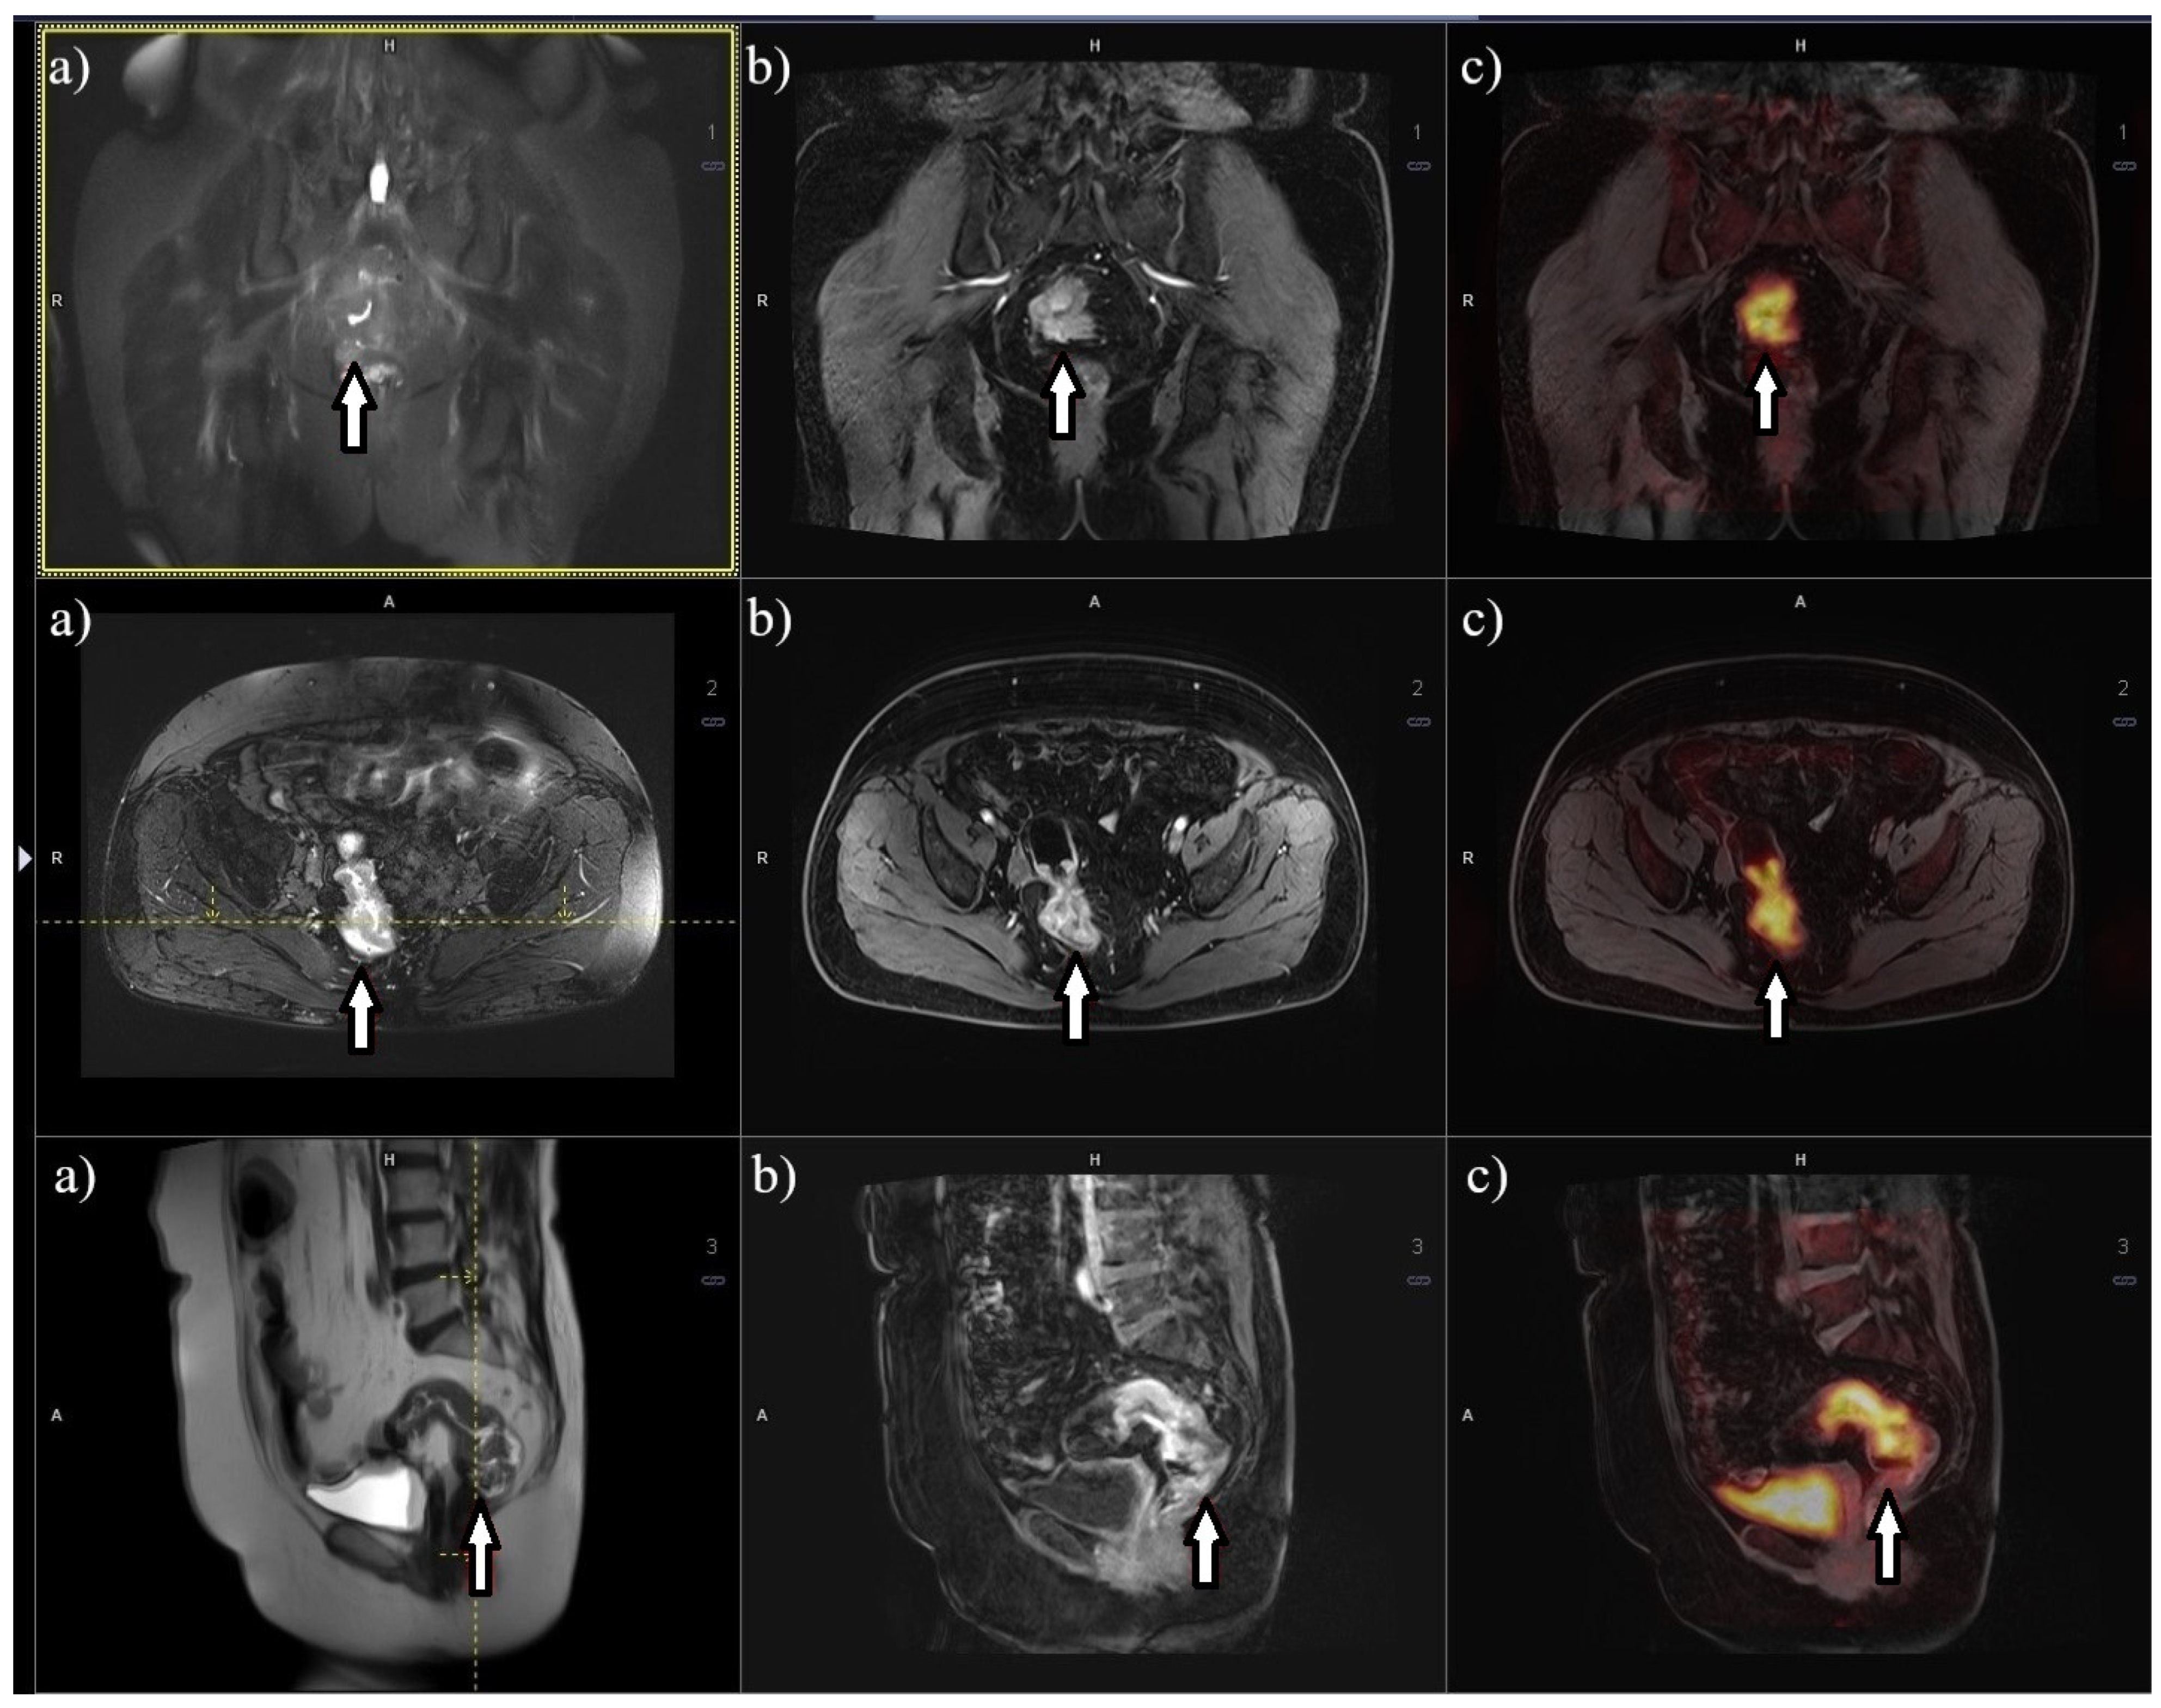

8. Metabolic Imaging 18F-FDG PET/MRI

- Rutegård, M.K.; Båtsman, M.; Axelsson, J.; Brynolfsson, P.; Brännström, F.; Rutegård, J.; Ljuslinder, I.; Blomqvist, L.; Palmqvist, R.; Rutegård, M.; et al. PET/MRI and PET/CT hybrid imaging of rectal cancer–description and initial observations from the RECTOPET (REctal Cancer trial on PET/MRI/CT) study. Cancer Imaging 2019, 19, 52. [Google Scholar] [CrossRef] [PubMed]

- Crimì, F.; Valeggia, S.; Baffoni, L.; Stramare, R.; Lacognata, C.; Spolverato, G.; Albertoni, L.; Spimpolo, A.; Evangelista, L.; Zucchetta, P.; et al. [18F]FDG PET/MRI in rectal cancer. Ann. Nucl. Med. 2021, 35, 281. [Google Scholar] [CrossRef]

- Bailey, J.J.; Jordan, E.J.; Burke, C.; Ohliger, M.A.; Wang, Z.J.; Van Loon, K.; Varma, M.G.; Hope, T.A. Does Extended PET Acquisition in PET/MRI Rectal Cancer Staging Improve Results? AJR Am. J. Roentgenol. 2018, 211, 896–900. [Google Scholar] [CrossRef] [PubMed]